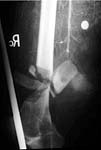

Case 1 - comminuted open supracondylar fx femur, no pulses, huge hematoma and bleeding. The angio shows popliteal artery transection. Immediately taken to OR where proximal and distal control are obtained prior to shunting. THEN Ortho ex-fixes the joint. The artery is definitively repaired. The wound is debrided. Later Ortho does a definitive ORIF with bone graft - successful.

Initial Angio

Transection Injury